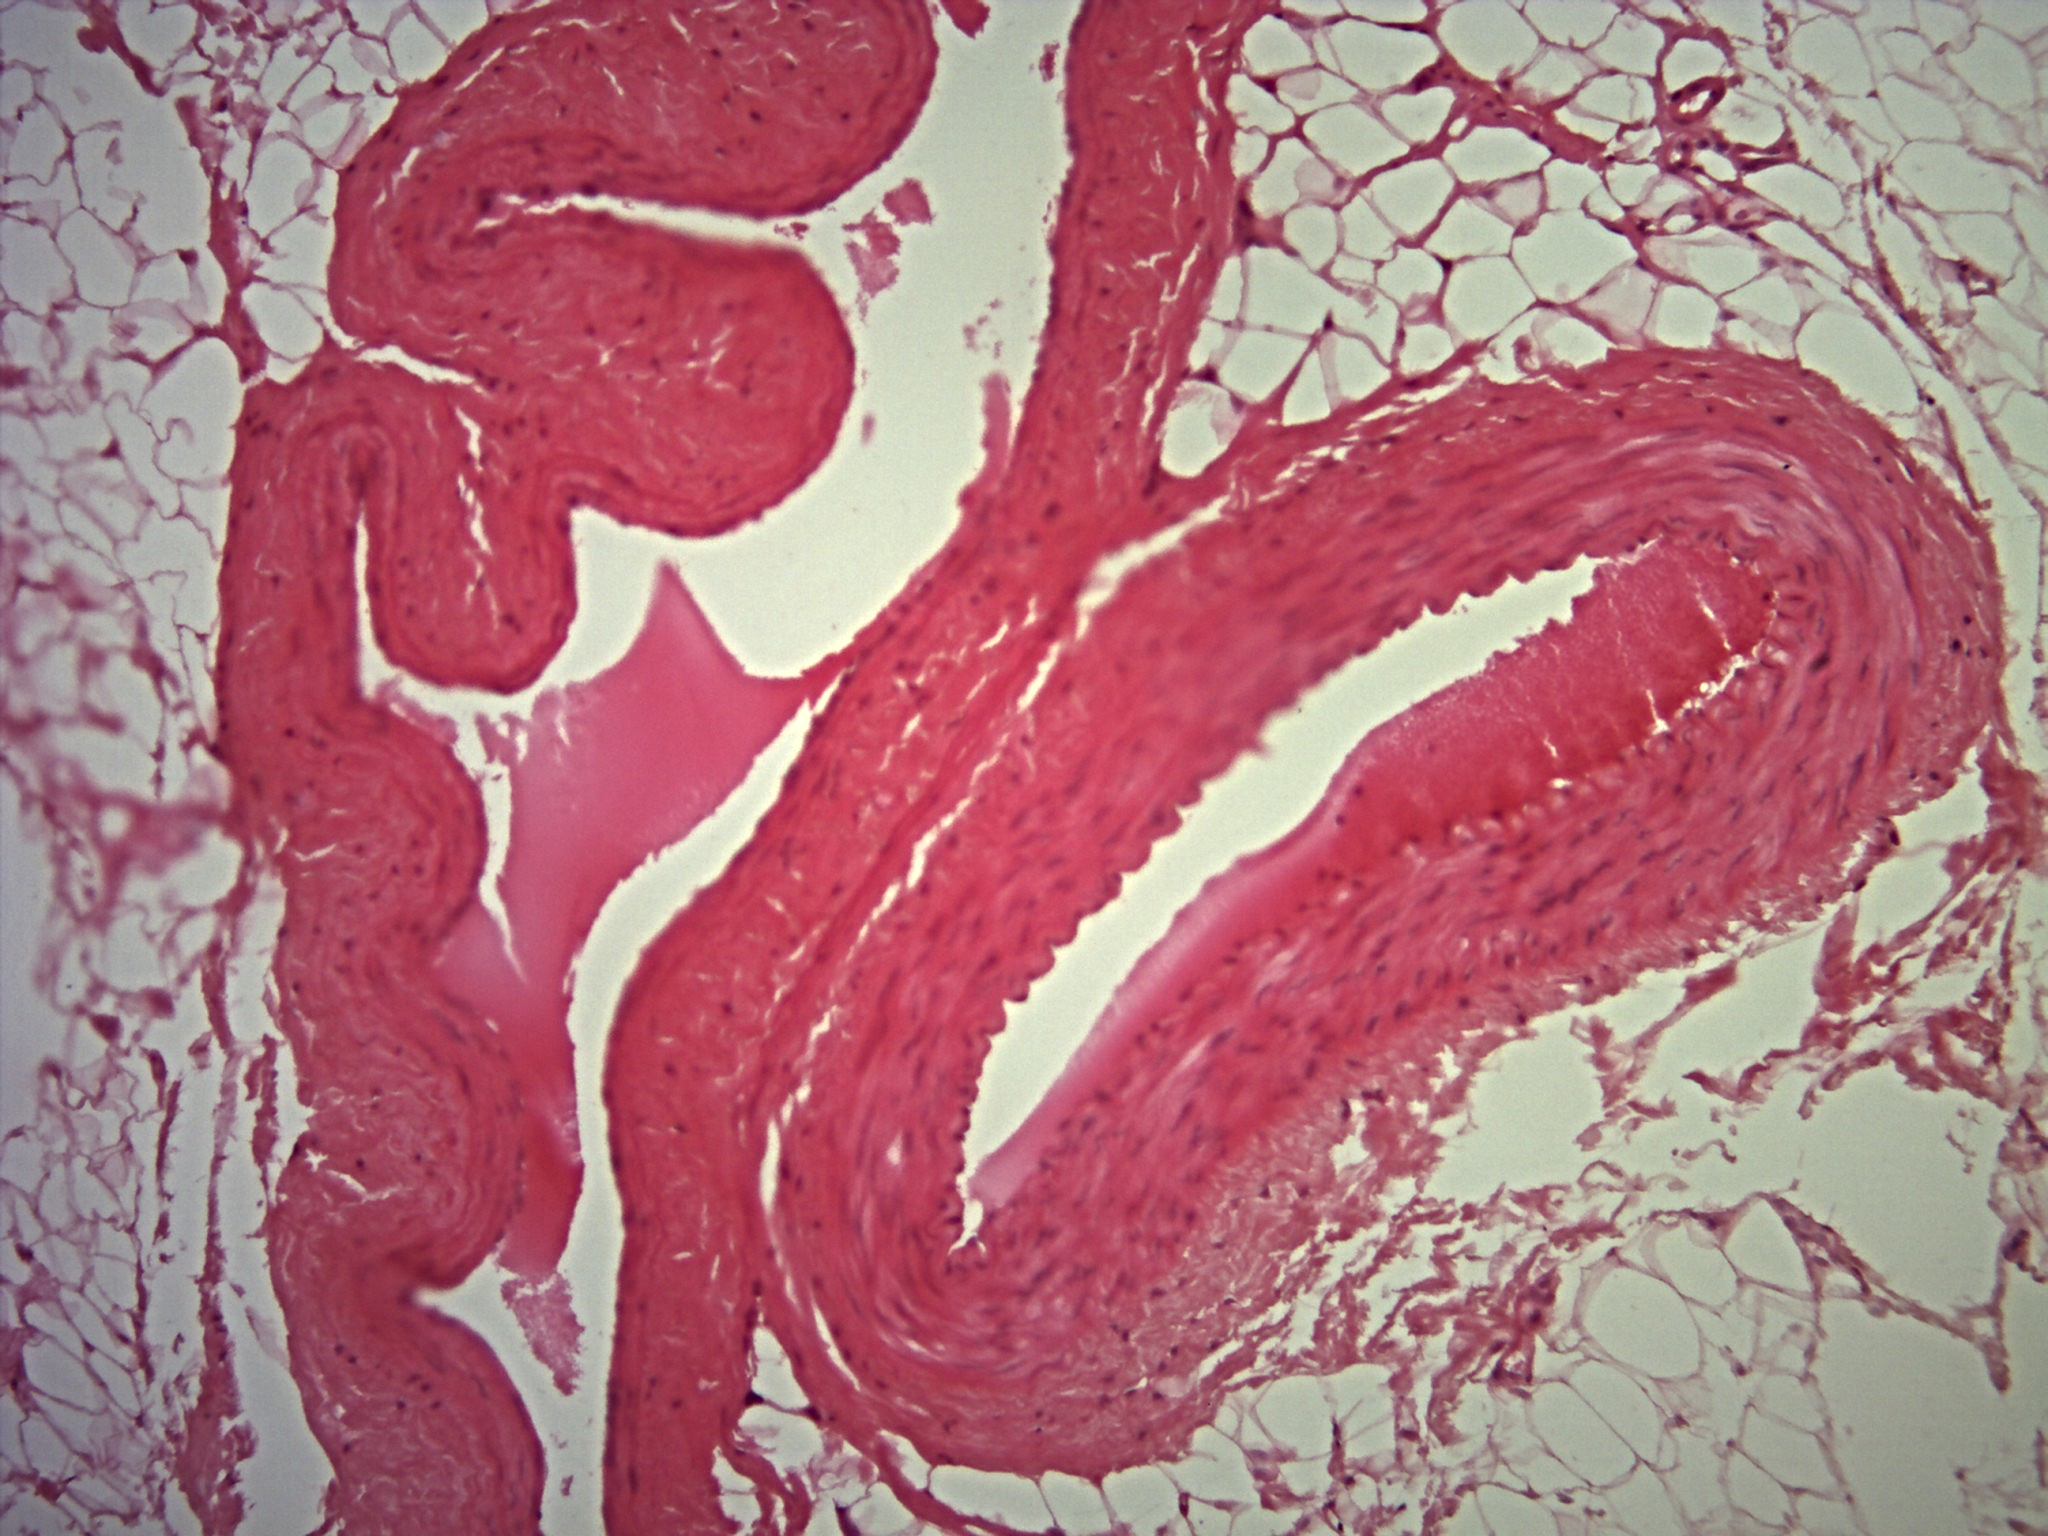

• Sistema Circulatório

Sistema Circulatório